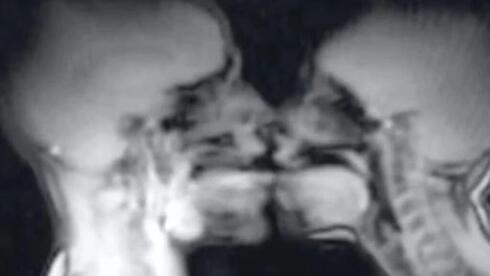

the study that transformed medicine’s view of the human body

1991 MRI Experiment Challenges Medical Assumptions Back in 1991, a woman and her partner participated in an unusual scientific study involving sex inside an MRI scanner. Fast forward over three decades, and the images obtained during this experiment continue to stimulate discussion in the medical community about human anatomy during intercourse. This study is often […]